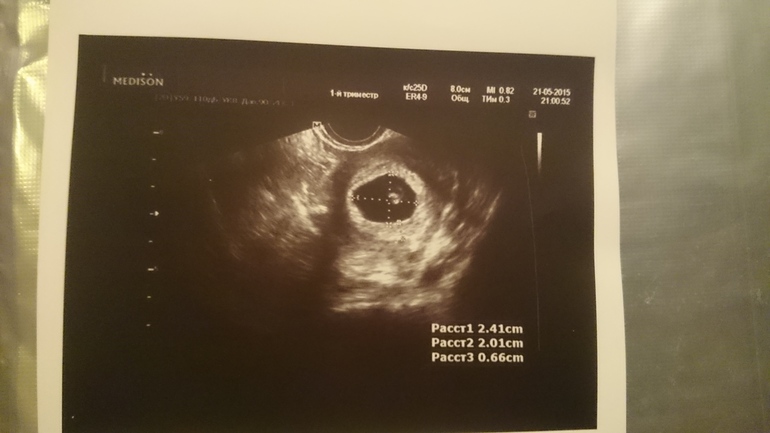

Второе УЗИ

Сходила на очередное УЗИ) Эмбрион на месте, шевелится и отбивает сердечком 140 ударов в минуту:))))

Срок малышу поставили чуть меньше чем по месячным. По месячным сегодня ровно 7 недель, по УЗИ 6+5. Но это даже к лучшему, так как ПДР сразу после нового года, а под куранты я рожать не хочу:)))

Под катом результаты и снимки с УЗИ